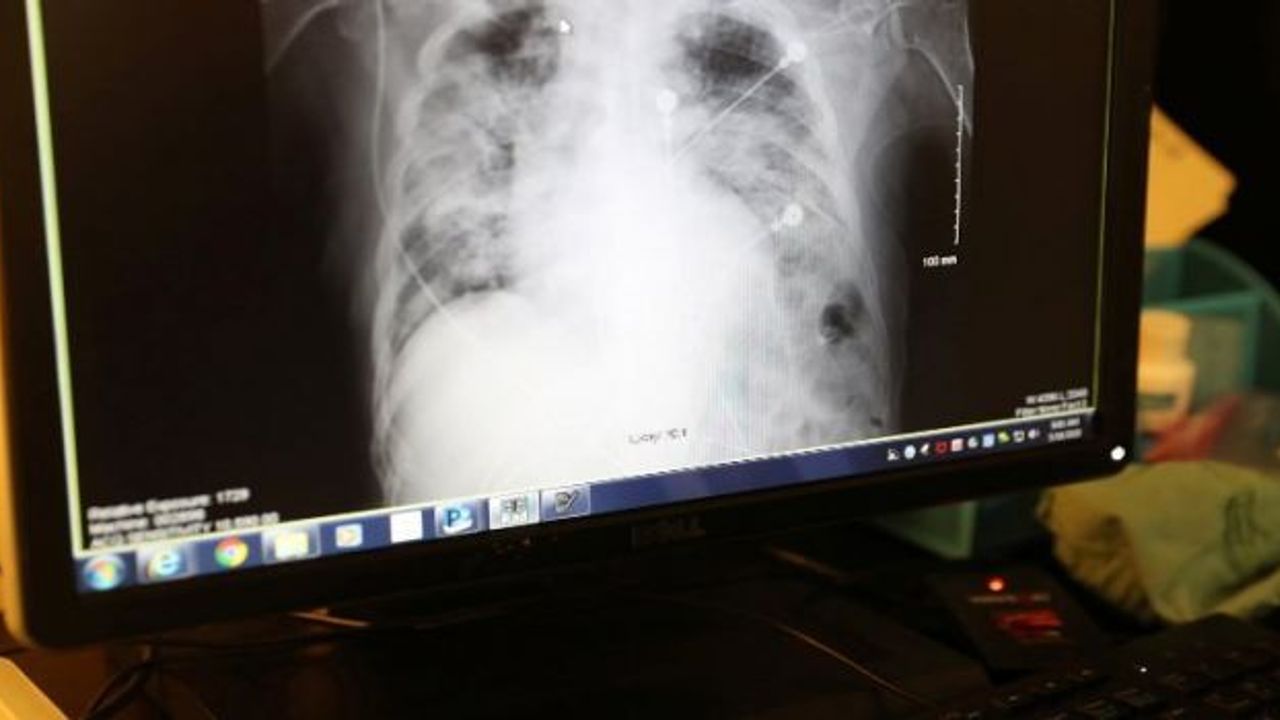

Korona virüsünün uzun vadedeki etkilerine ve iyileşme sürecine dair Avusturya’da yapılan bir araştırma, hastaneye yatırılması gereken hastaların akciğerlerindeki hasarın taburcu edilmelerinden haftalar sonra hâlâ geçmediğini ortaya koydu. Buna göre, hastaların solunum sıkıntısı ve öksürüğü de haftalarca devam ediyor.

* Hastaların yüzde 88’inin akciğer tomografisinde, taburcu olmalarından altı hafta sonra ‘buzlu cam’ görüntüsü dahil, hasar devam ediyordu;

* 12 hafta sonra çekilen tomografilerde akciğer hasarı görülen hastaların oranı yüzde 56 olarak tespit edildi;